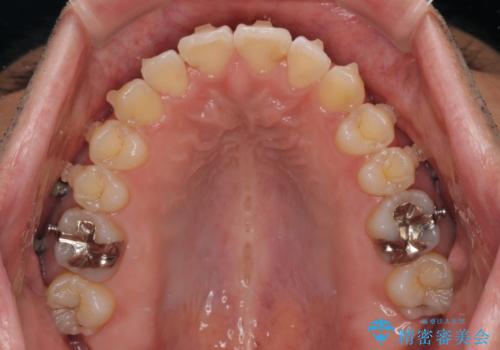

開咬とデコボコを整える インビザライン矯正治療

- 前歯の開咬と叢生を気にして来院された患者様です。

開咬の治療は、前歯を閉じるように動かすとともに、上下臼歯を圧下(骨内にめり込ませる)させることで進めて行きます。

インビザラインは臼歯の圧下を効果的に行えるため、インビザラインを用いて矯正治療を行うこととしました。また、アンカースクリューを用いて、口元の突出感の改善を図りました。